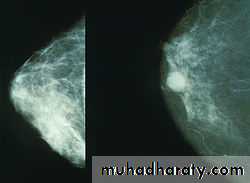

MAMOGRPHY

Its soft tissue radiographs are taken by placing the breast in direct contact with ultrasensitive film and exposing it to low voltage and high amperage x ray .the dose of radiation is approximitly 0.1 cGY,so its very safe investigation. the sensitivity of the test increase with the age as the density of breast decrease

Breast cancer tend to be more radio dense than the normal tissueCriteria that increase chance of cancer in patient without palpable mass appear in the mammography

1-microcalcification2-irregular mass with microcalcification 3- structural distortion with microcalcification 4- asymmetry with microcalcification 5- more than 5 microcalcification lcm2 6-indistict margin